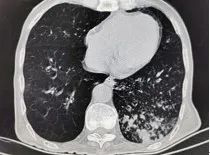

老年人肺炎混合感染不少见,但往往不易获得病原学,且病变隐蔽,因此仅行胸片检查往往易导致漏诊,有条件时需行胸部CT检查。胸部影像提示病变不典型,常呈小叶性病变而不是成年人肺炎常见的大叶性病变。